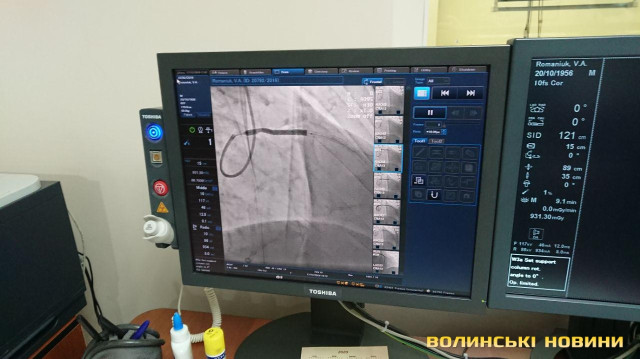

З 2013-го року реперфузійні центри працюють за системою «24/7», тобто ми допомогу надаємо у будь-який час і кожного дня. З 2018 року до цієї роботи долучився реперфузійний центр у м. Ковель завдяки ангіографу, встановленому за кошти субпроекту Світового банку. У нашому центрі щодня маємо 3-5 процедур. Також почали проводити тромбоекстракцію у пацієнтів з ішемічним інсультом. Це складна процедура, яку роблять у небагатьох клініках України. Суть у тому, що при інсульті треба вчасно відкрити судинку. У судину заводиться спеціальне обладнання і проводяться маніпуляції із видалення тромбу. Є випадки, що молодим людям ставало значно краще.